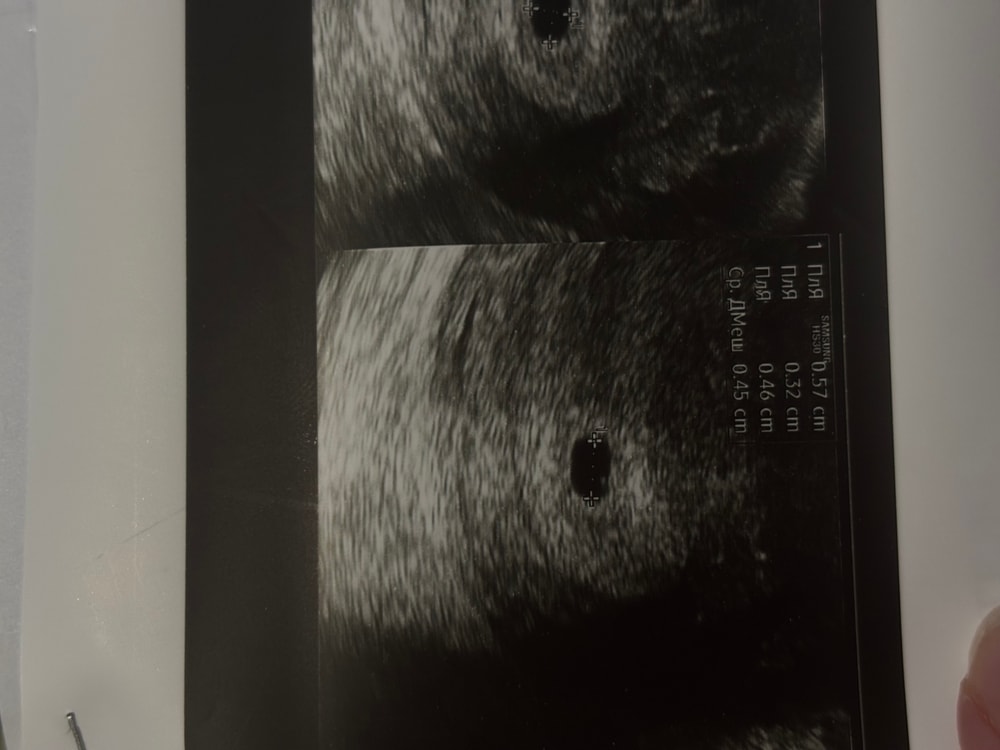

Нашли плодное яйцо в матке 🥳 4,5 мм . Срок 4 недели и 2 дня. Эмбрион пока не визуализируется (хотя мне показалось, что он там был: на фото видно слева что-то серенькое, спросила у Г она сказала что не знает что это такое , странно конечно)

24.06 171, 26.06 508, 28.06 1396

Больше не сдавала , пошла сразу на узи

Не может быть в таком пя эмбриона ещё, даже жм ещё не будет в таком пя,это очень маленький срок,сначала жм появиться,когда пя подрастет,а потом только эмбрион и сб

Может это желточный мешочек)